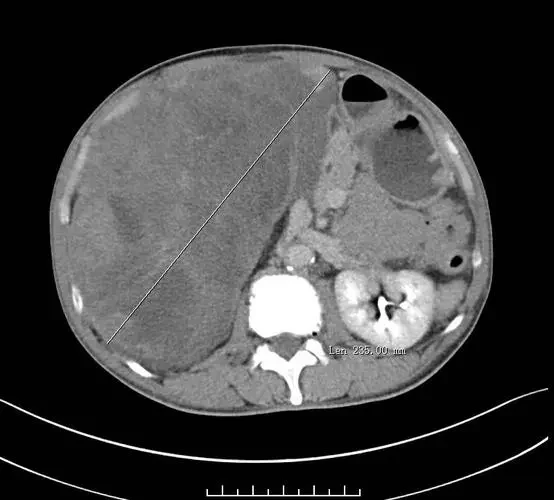

影像学检查在初步评估肿瘤性质方面也起到重要作用。CT扫描、MRI检查以及PET-CT等影像手段可以帮助医生了解肿瘤的位置、大小和形态特征,为进一步的病理检查提供方向。此外,影像学检查还可以了解肿瘤的局部扩展情况及是否存在远处转移。

影像学检查在疾病诊断中起到关键作用。CT和MRI是评估腹膜后肿瘤最常用的工具,可以提供关于肿瘤大小、位置及与周围组织关系的详细信息。PET-CT则可以用于评估肿瘤的代谢活性及是否存在远处转移。

影像学检查在肿瘤分期中起到关键作用。CT和MRI可以详细显示肿瘤的局部扩展情况及与周围重要器官的关系。PET-CT有助于评估远处转移情况。结合影像学检查结果,医生可以初步判断肿瘤的分期。